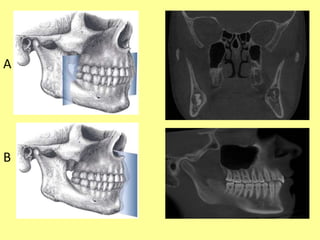

Imaging Studies

• Imaging studies are the basis for evaluation of

contemplated M3 removal.

• In addition to the depth of M3 within the

mandible (soft tissue, partial bone, and complete

bone impaction), and the angulation of the tooth

within the alveolar bone (vertical, horizontal,

mesioangular, distoangular), perhaps, the most

important information is the position of the tooth

roots in relation to the IAC.

• Four conditions can be identified:

(1) superimposition, in which the roots and IAC are

overlaid in the 2-dimensional radiograph but are

actually not in physical contact or proximity;

(2) notching of the root, in which the IAC is in intimate

physical contact within an indentation in the side of the

root;

(3) grooving, in which the IAC is in intimate contact

within a concave defect in the apex of the root;

and (4) perforation, in which the IAC actually

penetrates through the root .

• Conditions other than superimposition might

require further evaluation with a computed

tomographic scan .

Imaging Studies • Imagingstudies are the basis for evaluation of contemplated M3 removal. • In addition to the depth of M3 within the mandible (soft tissue, partial bone, and complete bone impaction), and the angulation of the tooth within the alveolar bone (vertical, horizontal, mesioangular, distoangular), perhaps, the most important information is the position of the tooth roots in relation to the IAC.

• Four conditionscan be identified: (1) superimposition, in which the roots and IAC are overlaid in the 2-dimensional radiograph but are actually not in physical contact or proximity; (2) notching of the root, in which the IAC is in intimate physical contact within an indentation in the side of the root; (3) grooving, in which the IAC is in intimate contact within a concave defect in the apex of the root; and (4) perforation, in which the IAC actually penetrates through the root .

• Conditions otherthan superimposition might require further evaluation with a computed tomographic scan .